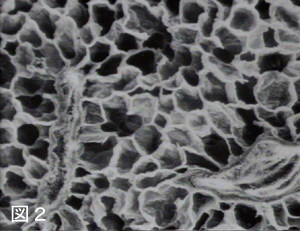

2.喫煙者の肺は空洞だらけになります

肺は肺胞の集まりから出来ており、スポンジ様の臓器です。〈 図 〉たばこの煙の有害物質によってじわじわと肺胞構造が壊されつづけて肺が空洞化してしまいます。

【健康な肺】 【肺気腫(喫煙者)】 肺の構造と肺胞の変化

健康な肺 肺気腫(喫煙者)

このような肺では、肺胞での換気が十分に行えなくなり、慢性的な酸素欠乏状態に陥り、呼吸困難や呼吸不全の原因になります。肺気腫の変化は喫煙者では30代、40代から始まることがわかってきました。他にも喫煙者は慢性気管支炎にもかかりやすくなります。